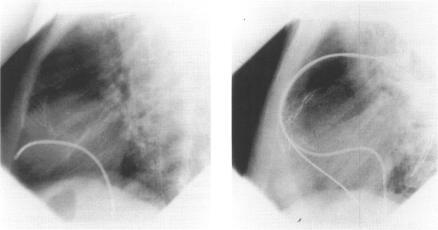

Raised plasma BNP in a patient with acute pulmonary thromboembolism.

Heart. 1997 Sep;78(3):320-1. doi: 10.1136/hrt.78.3.320-a.